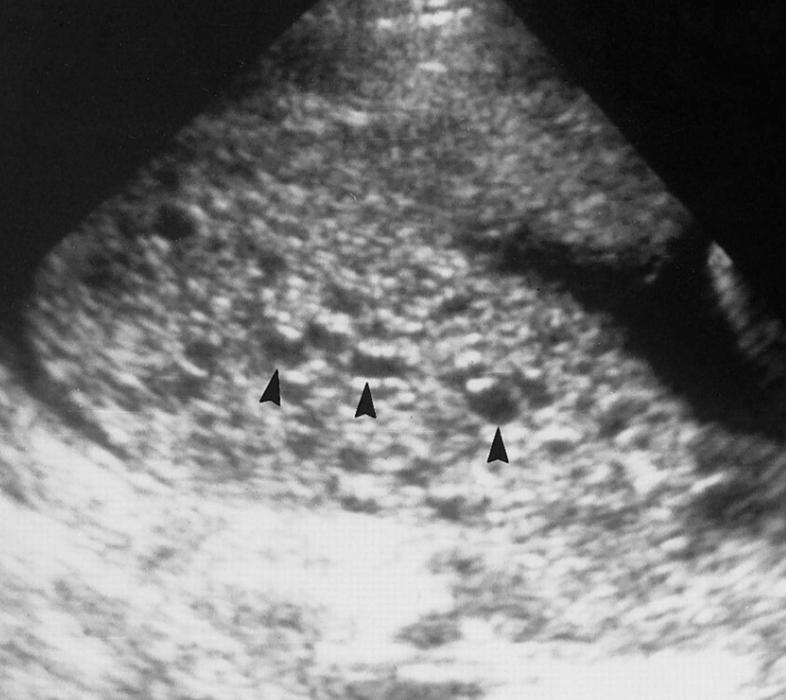

Медицина и диагностика: Инвазивный пузырный занос на УЗИ